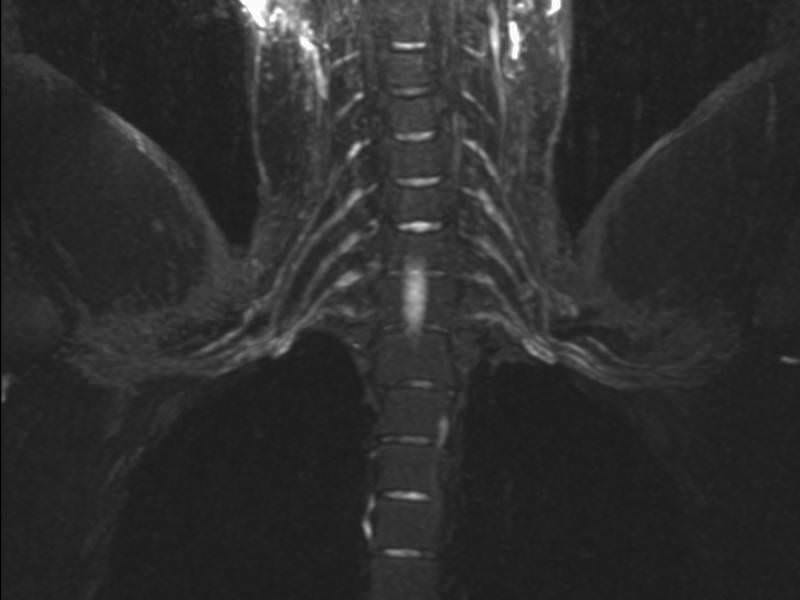

Here is another example: some imaging centers will perform isolated images of the brachial plexus, sometimes referred to as an MR neurogram.

Again, you can see the brachial plexus is bright, and the background is dark. Similar to the challenges of an isolated MRA, it is almost impossible to know if an adjacent structure is compressing or stretching the brachial plexus, because adjacent structures are intentionally suppressed. The NeoVista® MRI thoracic outlet syndrome test overcomes this limitation.

It is important to remember that none of these individual imaging components can tell the entire story by itself. TOS is complex and multi-factorial, and multiple contemporaneous imaging components are necessary to tell the entire story.